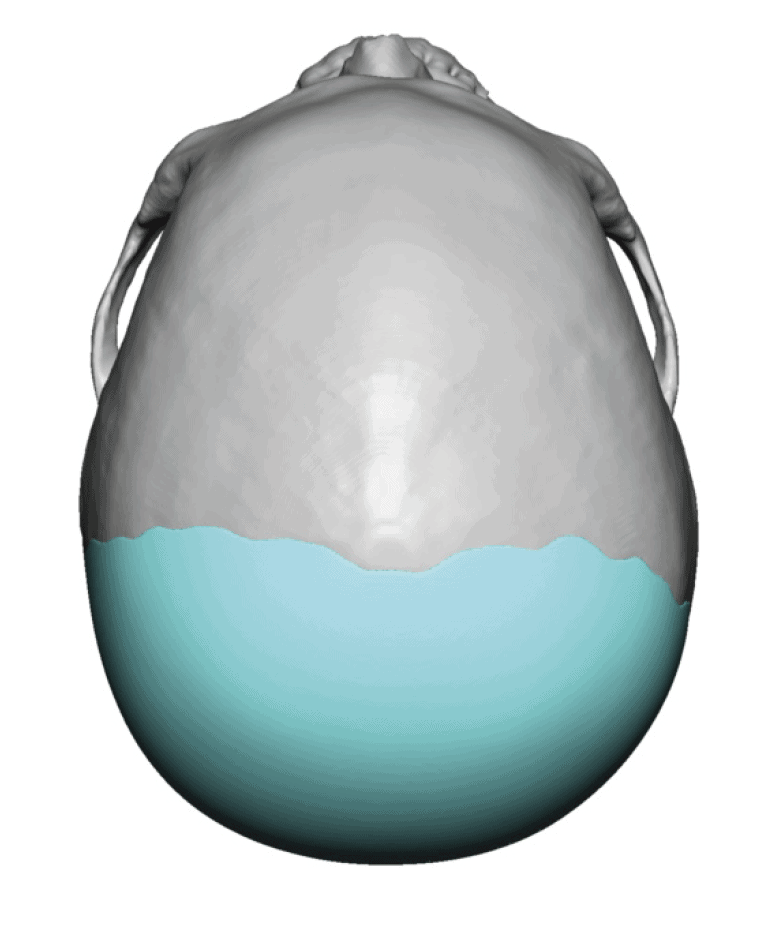

Patient 51

Desire for taller and rounder head shape.

Two stage custom skull implant augmentation technique.